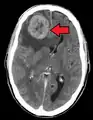

- Brain metastasis: neurological symptoms such as headaches,[9] seizures,[9] and vertigo[9]

Once a cancer has metastasized it may still be treated with radiosurgery, chemotherapy, radiation therapy, biological therapy, hormone therapy, surgery, or a combination of these interventions ("multimodal therapy"). The choice of treatment depends on many factors, including the type of primary cancer, the size and location of the metastases, the patient's age and general health, and the types of treatments used previously. In patients diagnosed with CUP it is often still possible to treat the disease even when the primary tumor cannot be located.